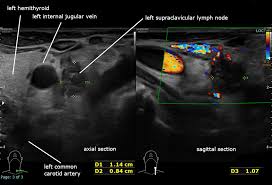

경동맥 초음파 검사는 고주파 초음파를 사용하여 목의 경동맥 혈관을 영상으로 확인하는 검사입니다. 혈관 내벽 두께, 혈류 흐름, 좁아진 정도 등을 실시간으로 볼 수 있으며, 조영제나 방사선 노출이 없어 안전합니다. 검사 시간은 약 20~30분 정도 소요됩니다.

1) 경동맥 협착증

경동맥 내벽에 콜레스테롤이 쌓이면서 혈관이 좁아지는 질환입니다. 뇌졸중의 주요 원인이 되므로 조기 발견이 매우 중요합니다.

혈관 내막 두께, 협착 정도, 혈류 속도 등을 확인할 수 있으며, 결과에 따라 추가 정밀검사가 필요할 수 있습니다.